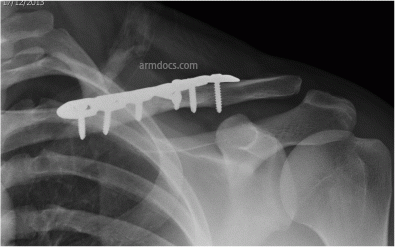

b. Appearance after fixation with a plate